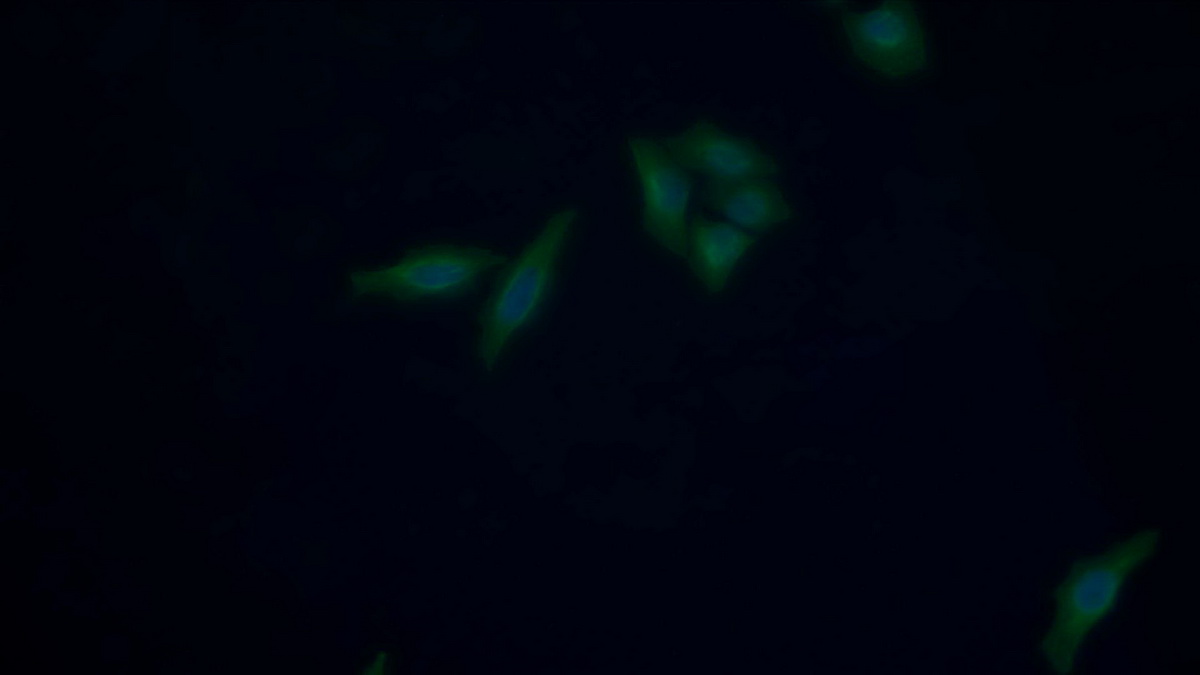

| Applications | WB; IHC; ICC; IP. |

Enolase, Neuron Specific (NSE) Human Monoclonal Antibody